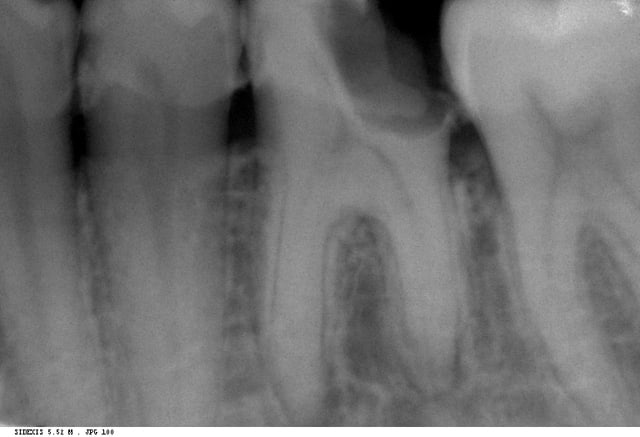

je vous envoie cette radio qui n'est pas la plus explicite des cas qui me tracassent, mais si on a une carie distale trés délabrante et que la dent avoisinante se verse mésialement de façon a combler la cavité de carie, il faut extraire ou traiter ? et dans ce cas comment se fait l'obturation coronaire convenable et la bonne restitution du point de contact ?

tu dois pouvoir la conserver cette dent,le problème n'est pas tellement le point de contact,que cette carie trop profonde pour espérer raisonnablement ne pas dévitaliser,et l'etat de calcification apparente des canaux qui laisse presager quelques difficultés de traitement

heu... vu le délabrement conséquent + le potentiel de vitalité pulpaire résiduel qui doit être au ras des paquerettes, je ne me risquerai pas à tenter de garder la vitalité pulpaire.

La pulpe doit certainement souffrir un max. L'élargissement ligamentaire ne laisse rien présager de bon.

Donc bio + reonstitution à tenon de type IC (because délabrement +++ et profond) + coiffe.

En apical de la racine distale je me demande même si l'élargissement ligamnentaire ne serait pas un début de pathologie péri apicale non?...

Garder "vivante" cette dent me parait plus que risqué...Et je pense même qu'on a peut être une nécrose partielle. Que donne le test de vitalité?